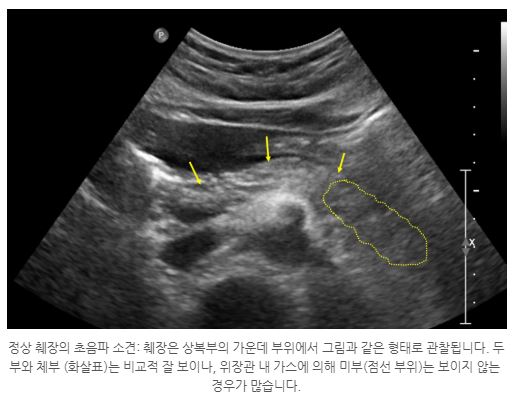

고로 이런 어정쩡한 통증이 있다라고 하면 빨리 검사를 받아보시는 편이 좋아요. 현재까지 췌장암 조기 증상에 관해서 말씀드렸는데요. 그럼 최장검사는 어떻게 할까요? 사실 최고 일전에 쉽게 해 볼 수 있는 검사가 복부 초음파 검사이예요. 초음파 검사는 배에 초음파 진단기를 문지르면서 보는 것이라서 간단하고 쉽게 가능한 검사입니다. 췌장을 잘 볼 수 있다고 한다면도 있다고하지만 췌장을 정확히 보기 힘든 경우도 있고요.

예컨대, 복부 비만이 있으시다면에는 초음파로 췌장의 전체 모양을 확인하기가 무척 어렵습니다. 뒤집어서 배에 살이 없으며 마른 경우에는 잘 보이예요. 또 위나 장에 가스가 많이 있는 처지에서도 초음파로 췌장을 확인이 완연하게 하기가 어렵습니다. 그리하여 사람에 따라서 가스 정황에 따라서 잘 보일 수도 있고 잘 안 보일 수도 있죠.